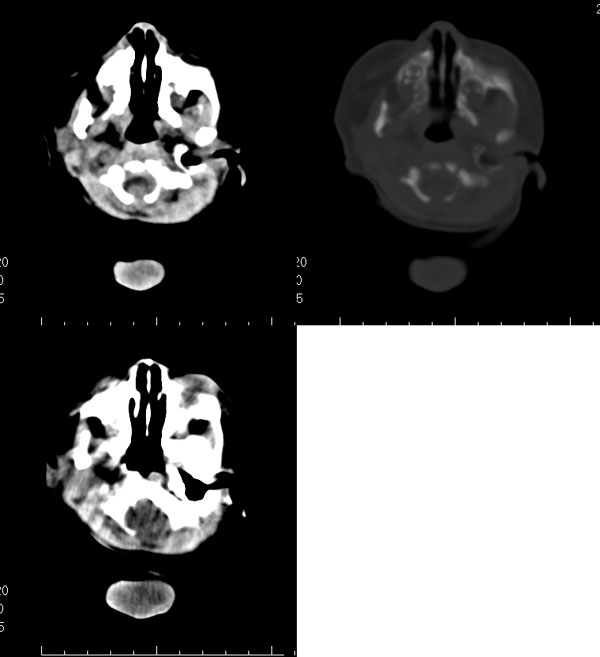

2天,枕部肿物

枕骨缺损,脑膜脑膨出。同时第4脑室挤压变形、闭塞,致使第3脑室、双侧侧脑室显著积水、扩张,过高的颅内压推挤脑实质,致使颅骨内板出现多而且深的脑回样压迹,脑细胞水肿,皮质、白质分界不清。

考虑先天性中脑水管梗阻,其以上脑室扩大。枕部脑膜脑膨出!

枕骨脑裂畸形伴脑膜脑膨出,双侧脑室扩张积水,第四脑室变窄致使双侧侧脑室及第三脑室积水,

枕骨缺损,脑膜脑膨出。同时第4脑室挤压变形、闭塞,致使第3脑室、双侧侧脑室显著积水、扩张.